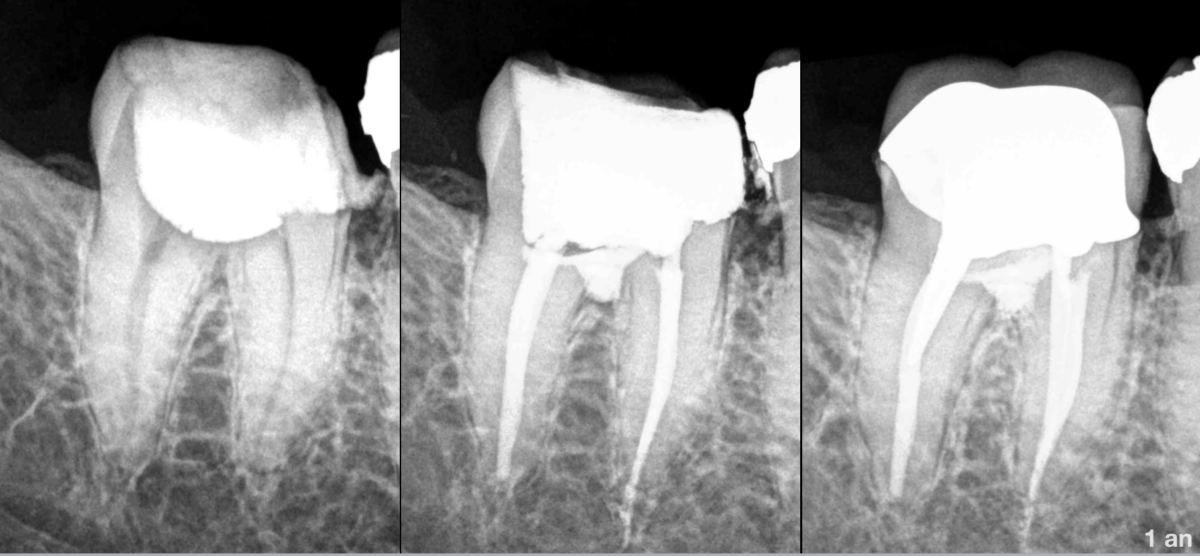

- Traitement précédemment initié

- 𝐎𝐬 𝐩𝐞́𝐫𝐢–𝐚𝐩𝐢𝐜𝐚𝐥 𝐧𝐨𝐫𝐦𝐚𝐥

- Perforation de la furcation.

𝐓𝐫𝐚𝐢𝐭𝐞𝐦𝐞𝐧𝐭 𝐜𝐚𝐧𝐚𝐥𝐚𝐢𝐫𝐞 + traitement de la perforation.

🔹 𝐌𝐚𝐭𝐞́𝐫𝐢𝐚𝐮 𝐛𝐢𝐨𝐜𝐞́𝐫𝐚𝐦𝐢𝐪𝐮𝐞 (dans ce cas 𝐓𝐎𝐓𝐀𝐋𝐅𝐈𝐋𝐋 𝐅𝐚𝐬𝐭 𝐒𝐞𝐭 𝐏𝐮𝐭𝐭𝐲, 𝐅𝐊𝐆, distribué par Acteon)

🔹 𝐏𝐫𝐨𝐭𝐞𝐜𝐭𝐢𝐨𝐧 𝐝𝐞 𝐥𝐚 𝐳𝐨𝐧𝐞 𝐜𝐨𝐧𝐜𝐞𝐫𝐧𝐞́𝐞 par un 𝐂𝐕𝐈𝐌𝐀𝐑